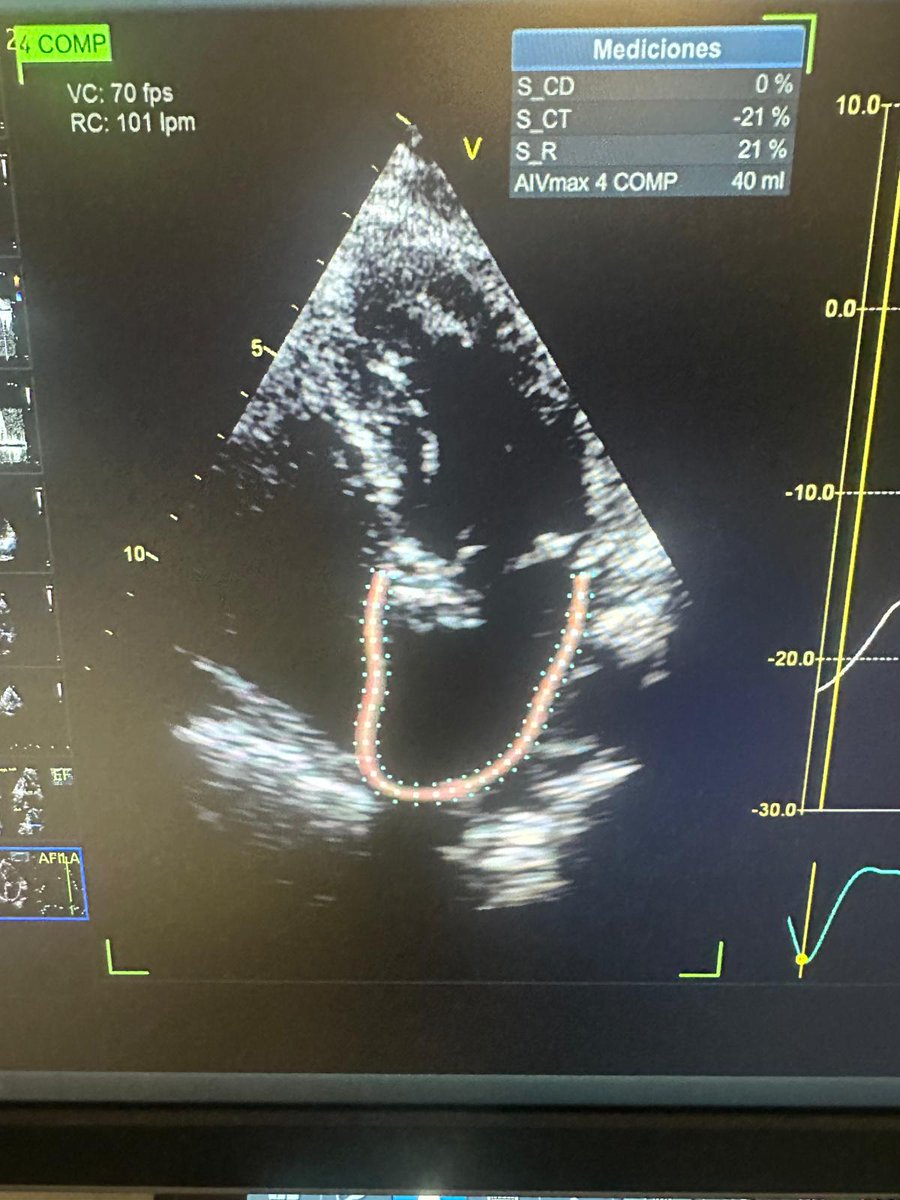

We had the pleasure and privilege to perform a live case @ Sanatorio Anchorena showing a small annulus #TAVI patient w/ small annulus with #EvolutPro+ @MDT_StructHeart. Great result with the mentoring of @msztejfman & Vero González